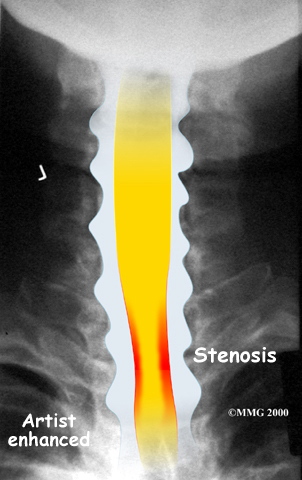

The bony spinal canal normally has more than enough room for the spinal cord. Typically, the canal is just less than ¾ of an inch, or 17-18 millimeters around, which is less than the size of a small bottle cap. Spinal stenosis occurs when the canal narrows to around half an inch, or 13 millimeters or less. When the size drops even further, severe symptoms of myelopathy occur. The symptoms of myelopathy result from the actual pressure against the spinal cord itself as well as the reduced blood supply in the spinal cord as a result of the pressure.